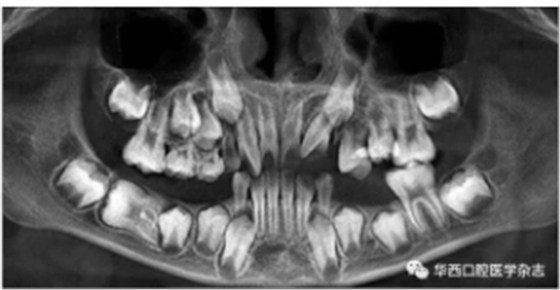

全景片及錐形束CT(cone beam computed tomo-graphy,CBCT)三維重建影像顯示:46牙胚存在,牙冠朝向遠中,且牙長軸與下頜骨下緣接近平行,遠中根發(fā)育約為根長2/3,近中根發(fā)育約為根長1/2且稍向下彎曲,近中根與45牙關(guān)系密切,下頜其余牙胚正常(圖2、圖3)。

圖 3 治療前CBCT三維重建